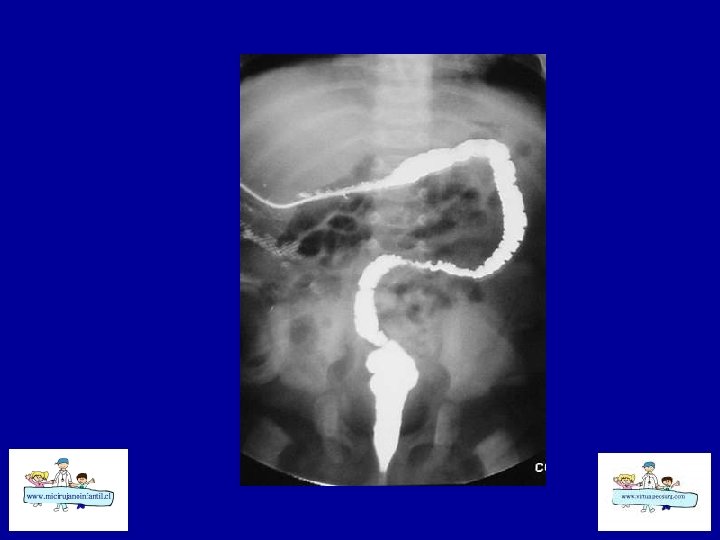

ECN - SECUELAS • Estenosis intestinal (cicatrización de pared isquémica) • Su frecuencia ha aumentado en los últimos años (14 – 36 %), mayor en etapas avanzadas • Siempre sospechar y se debe descartar • Distensión abdominal, bajo peso, intolerancia alimentaria, dolor, hematoquezia, sepsis.

ECN - SECUELAS • • Intestino Corto Bridas Estenosis de colon Secuelas de prematurez: Desnutrición, Retraso del lenguaje y del DSM